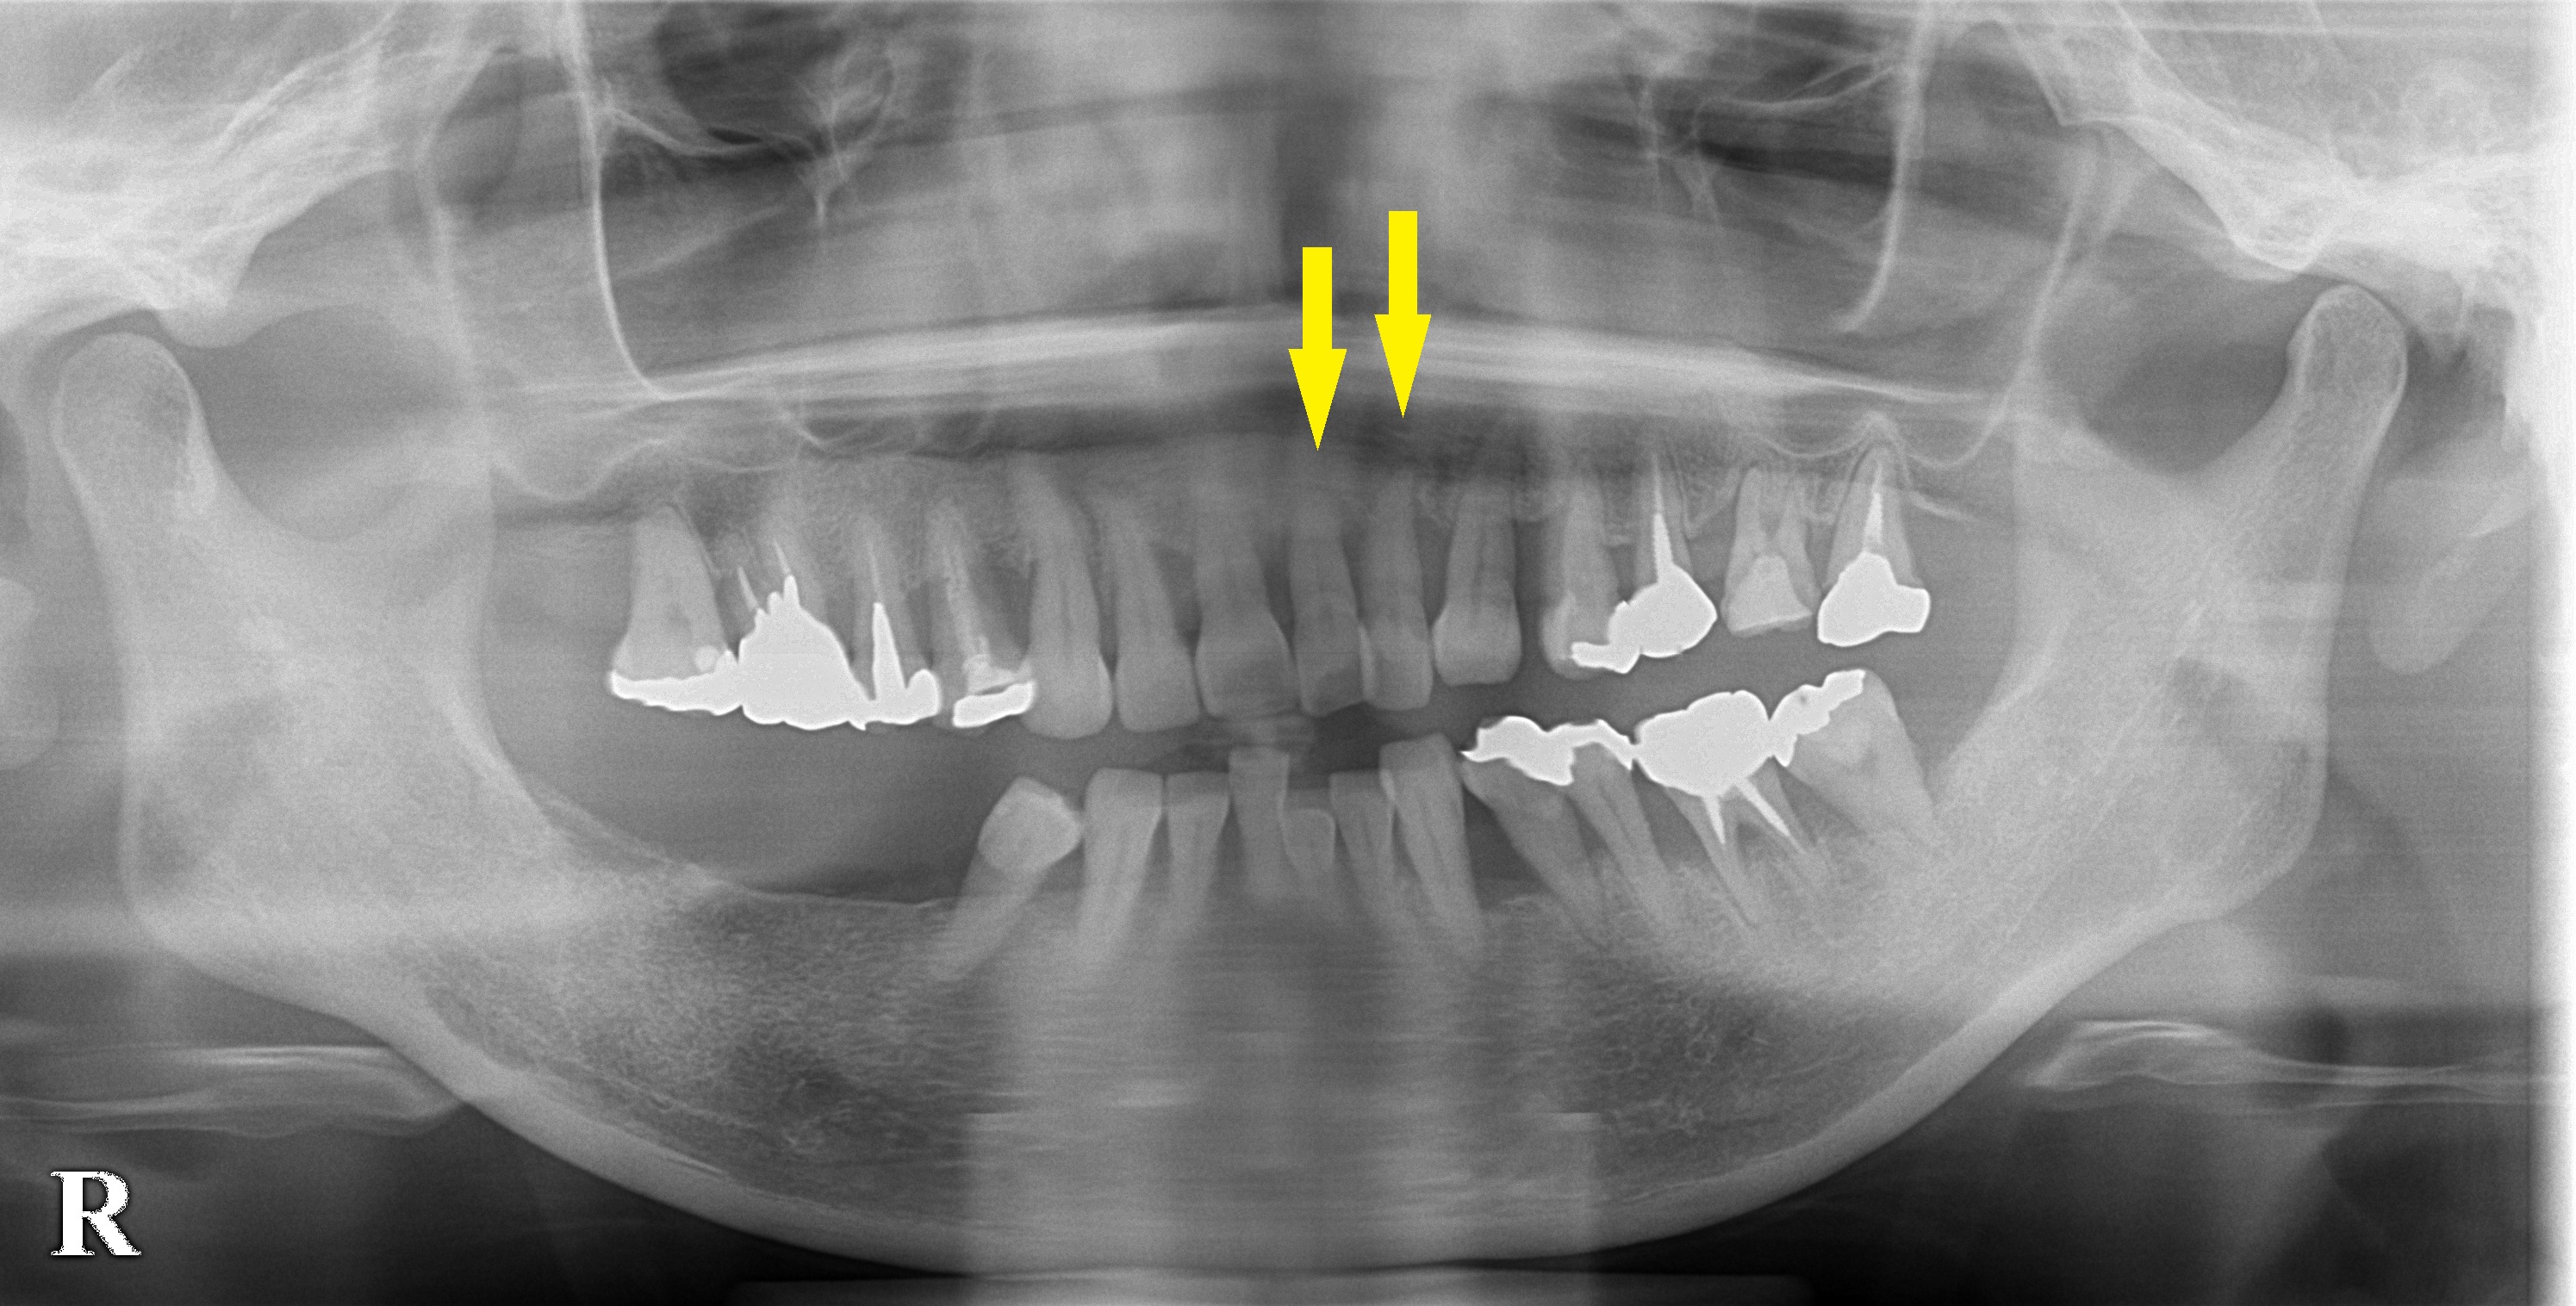

左側の上顎前歯2本がグラグラになっておりインプラント治療を希望されて来院されました。

重度の歯周病で、歯を支える歯槽骨が大きく吸収されてしまっていて、保存は難しいと考えられました。

前歯ですので、仮歯もしっかり入れたいということで、抜歯して即時インプラント埋入を行い、さらに、そのまま固定式の仮歯を装着する即時修復を予定しました。